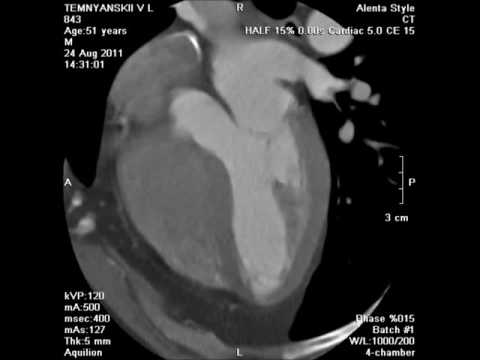

ПЕРЕЛОМ 10 РЕБРА слева и РАК ЛЕГКИХ на КТ расшифровке (второе мнение)

Компьютерная томография (КТ) грудной полости

Повторная расшифровка КТ показывает МЕТАСТАЗЫ В РЕБРАХ при аденокарциноме прямой кишки

Мультиспиральная КТ в диагностике тупой торакальной и абдоминальной травмы